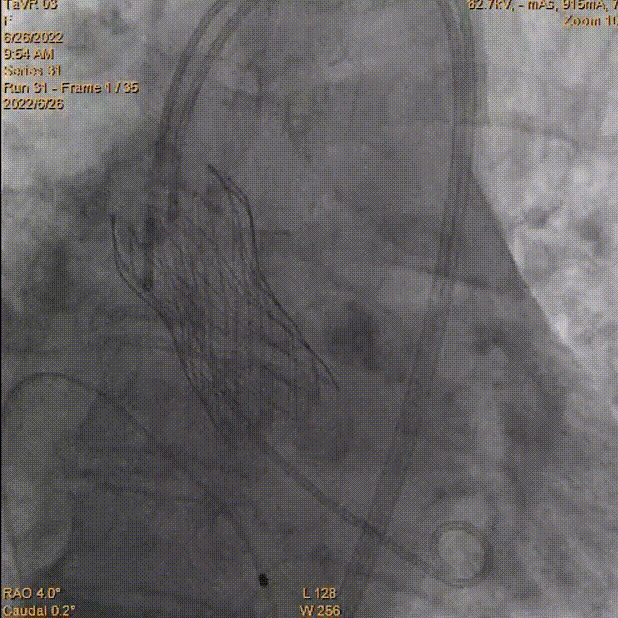

术中影像:

主动脉根部造影

瓣膜释放至工作位

完全释放到达理想状态

术后主动脉根部造影压差为8mmHg